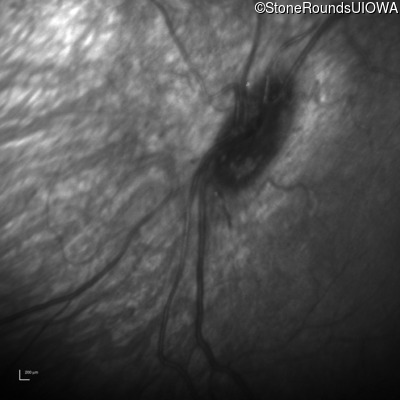

Infrared Fundus Photograph - Right -

No Light Perception

Exemplar

Infrared Fundus Photograph - Left -